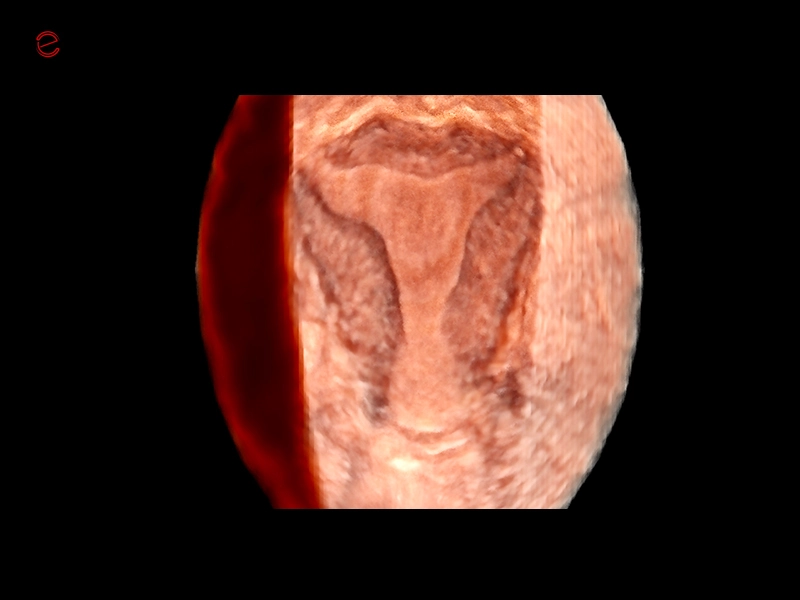

MyLab™C30 - Gyn 3D

MyLab™C30 - Gyn 3D